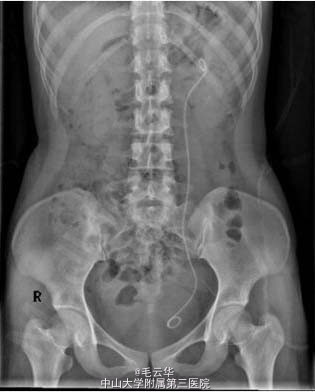

术后辅查KUB示未见结石残留。予办理出院,嘱1月后返院拔管。讨论:随着医疗科技的迅速发展,泌尿系结石的治疗设备和操作技术日益更新,输尿管软镜以其微创、安全、有效、并发症少、术后恢复快等优点在肾结石治疗发挥越来越重要的作用。输尿管软镜碎石特别适用于治疗直径<20 mm的肾结石患者、老年体弱者、极度肥胖者、出血性疾病者和不适合采取体外冲击波碎石术(ESWL)和经皮肾镜取石术(PCNL)治疗的患者;甚至对于>2cm铸型甚至鹿角型结石也具有良好的治疗效果。尽管目前输尿管软镜容易损坏且维修费用昂贵的问题制约了其大规模推广应用,但输尿管软镜正越来越受到广大泌尿外科医师的重视,仍将具有良好的发展前景。